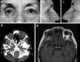

Orbital metastasis